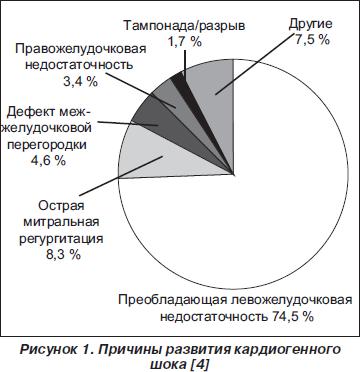

Уровень летальности у пациентов с КШ определяется целым рядом демографических (возраст), клинических (признаки периферической гипоперфузии, олигурия, гипоксия и повреждение головного мозга), гемодинамических факторов (фракция выброса ЛЖ, ударный объем сердца), а также непосредственной причиной развития острой сердечной недостаточности. Причинами КШ могут быть поражение левого или правого желудочков сердца, внутренний или наружный разрыв миокарда, а также поражение клапанного аппарата сердца (рис. 1).

Основной причиной КШ у пациентов с ОИМ является дисфункция левого желудочка, которая совместно с нарушением насосной функции правого желудочка отмечается примерно у 80 % всех пациентов. У этой категории больных проведение ранней реваскуляризации миокарда позволяет существенно снизить риск внутри- и постгоспитальной смерти независимо от возраста, пола и других факторов риска [3].